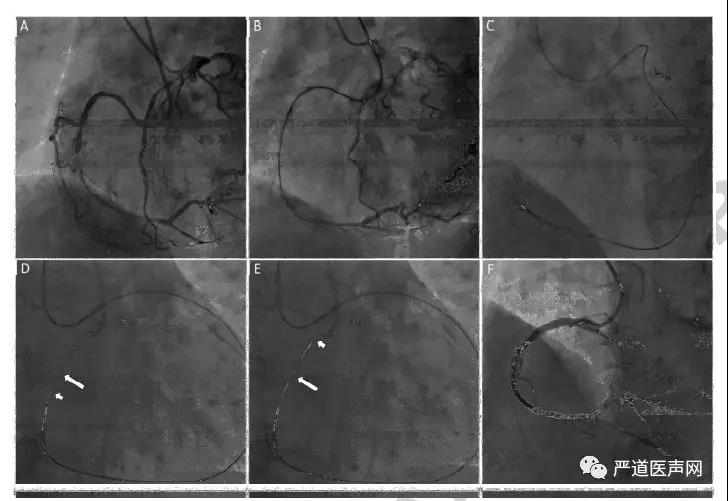

病例二:68岁男性,多支病变,有严重心绞痛,危险因素包括高血压和吸烟。2003年曾于RCA植入1枚支架,此次症状发作后当地医院拟开通RCA CTO失败。使用6 Fr AL0.75 指引导管(Medtronic) 和 6 Fr EBU 3.5指引导管 (Medtronic)。前向失败后尝试逆向开通(b,c)。逆向导丝成功通过闭塞段,逆向导丝向前置入前向指引导管的过程非常困难。前向置入Guidezilla™扩展导管(长箭头)并尽可能向远端送,与逆向导丝(短箭头)相遇(d)。在Guidezilla™扩展导管的帮助下,逆向导丝很容易地进入了前向指引导管(e)。术后复查造影RCA CTO开通(f)。